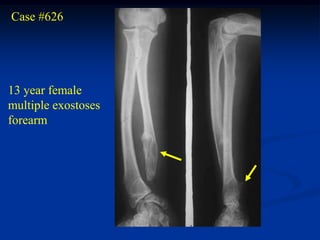

Case #626

13 year female

multiple exostoses

forearm